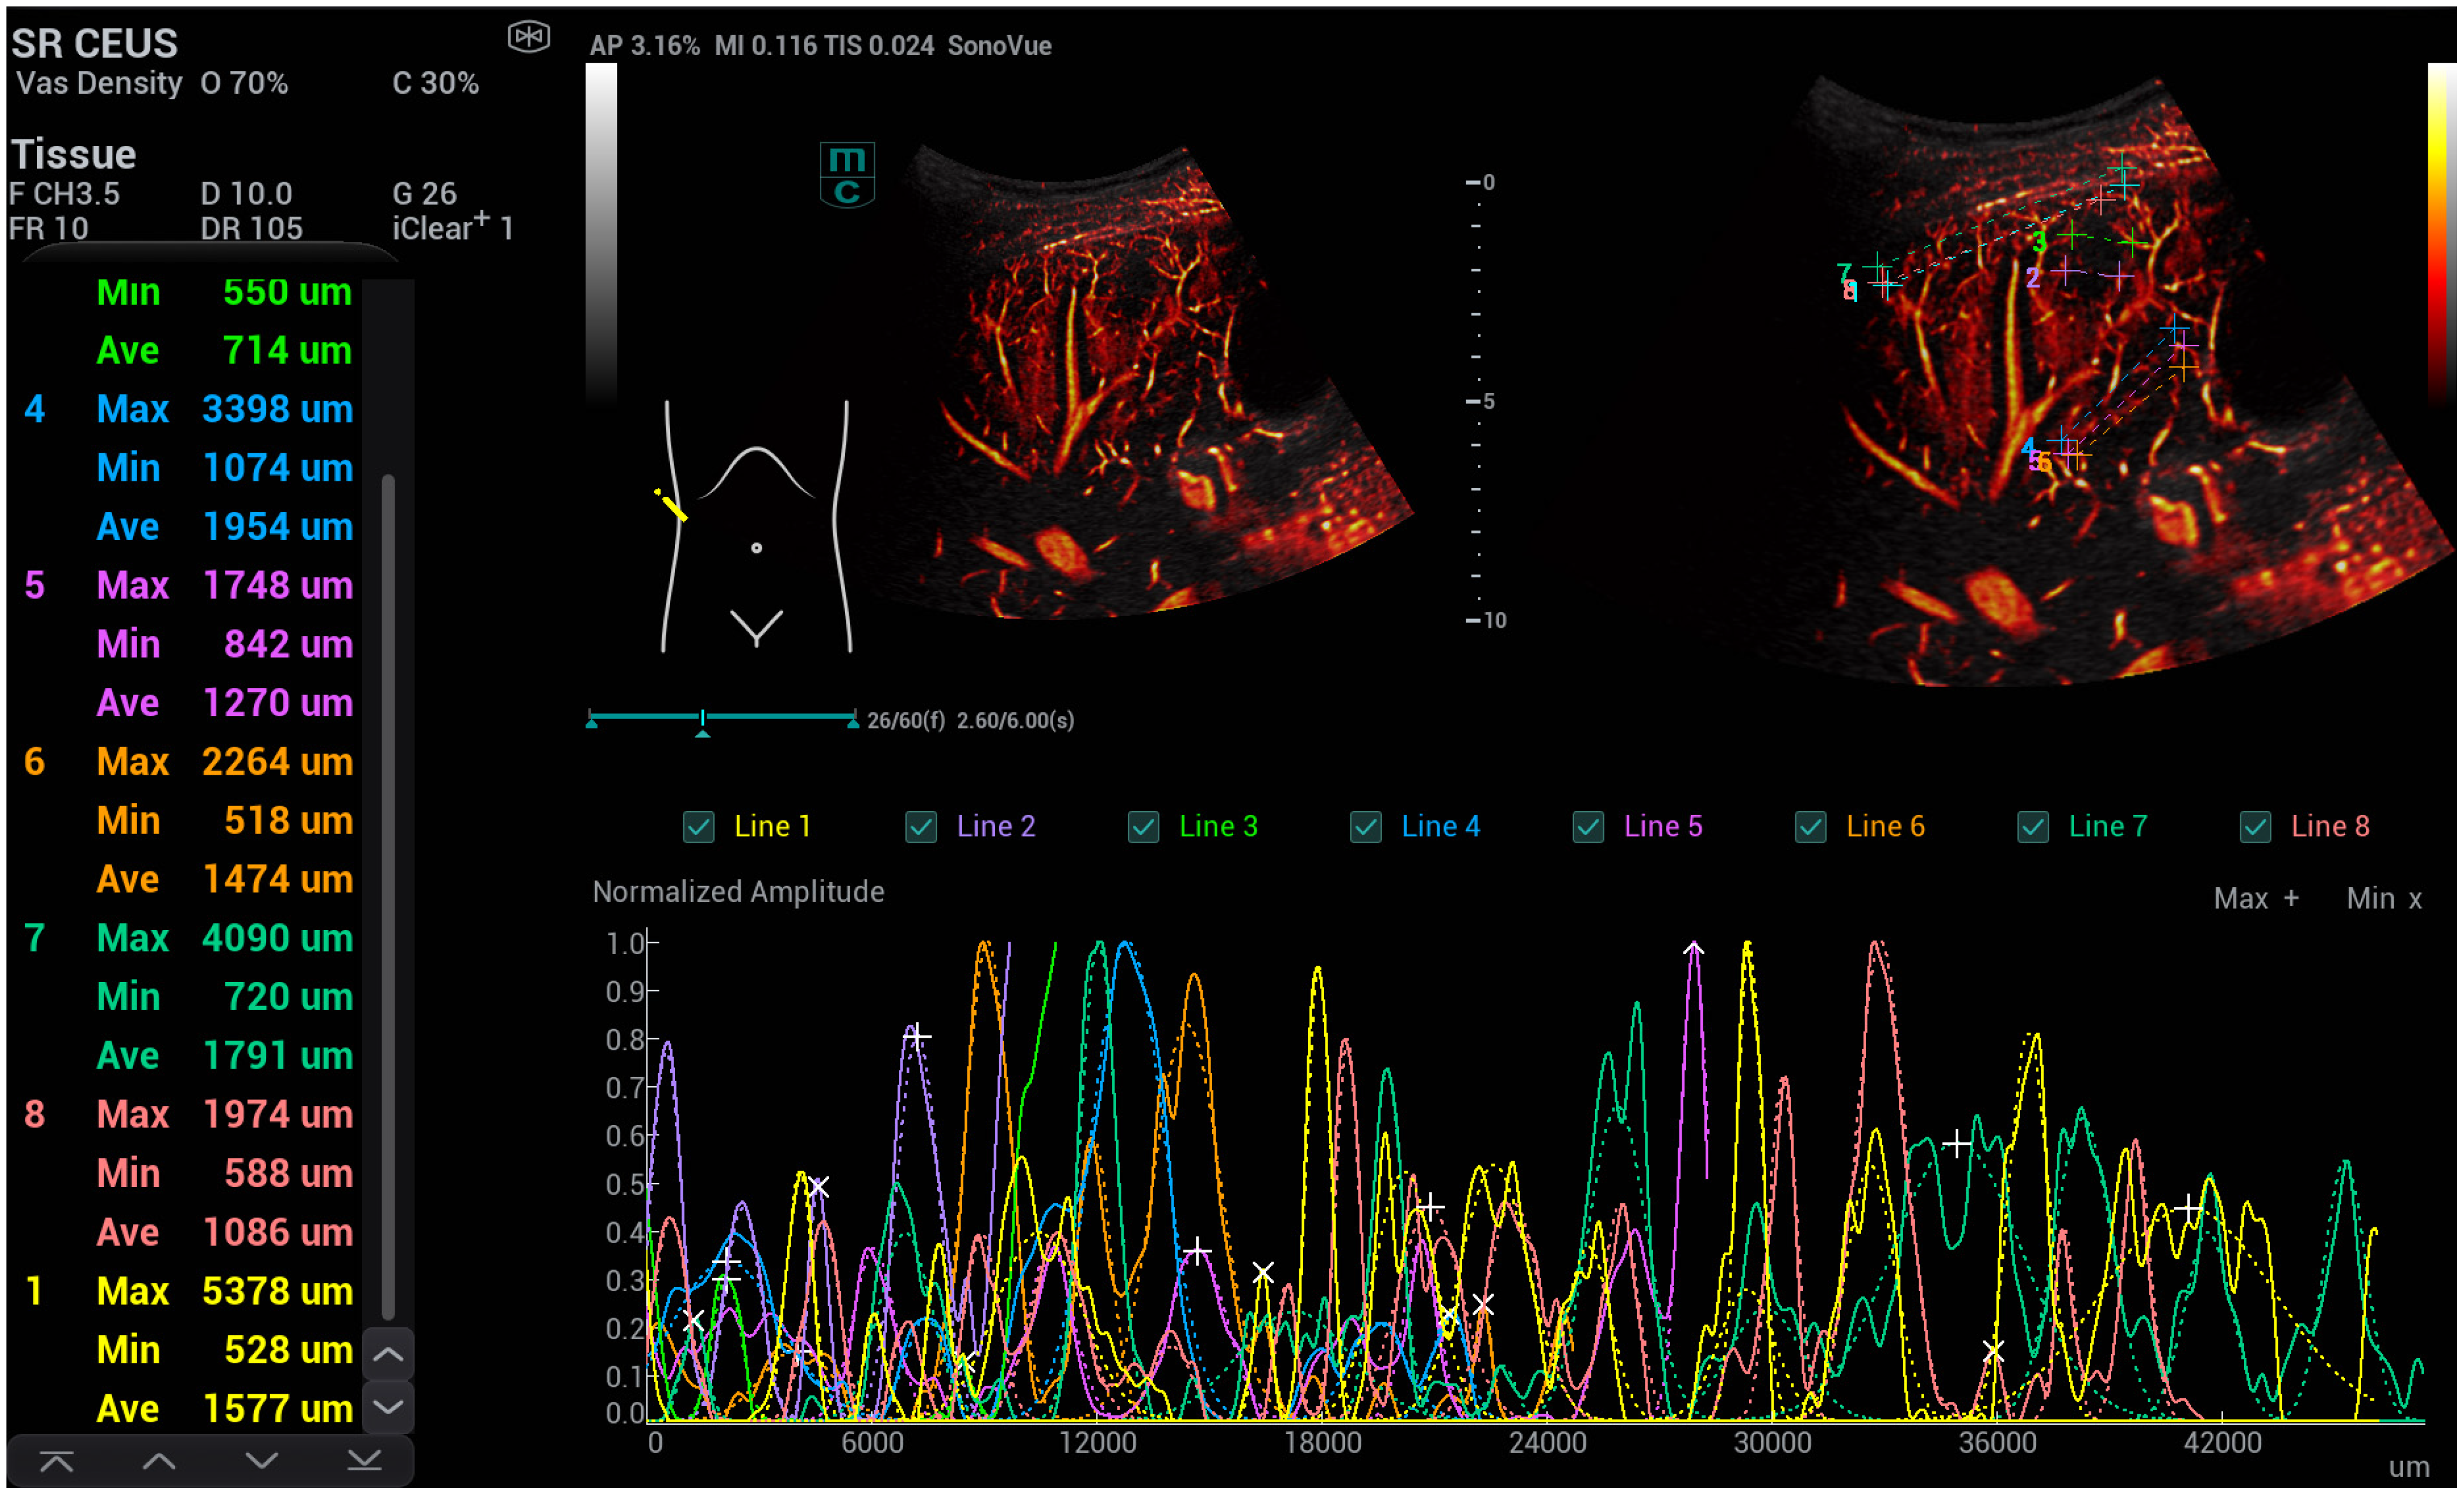

High-Resolution Contrast-Enhanced Ultrasound with SRCEUS for Assessing the Intrahepatic Microvasculature and Shunts in Patients with Hereditary Haemorrhagic Teleangiectasia (Osler’s Disease)

3. Results

| diameter: close to the capsule | 5133.7 ± 1456.6 | 1972.3 + 399.2 | 6.18989 × 10−13 |

| diameter: at the level of the portal vein | 2175.3 ± 417.5 | 2890.7 + 606.9 | 3.00779 × 10−11 |

| area: close to the capsule | 68.9 ± 8.8 | 8.9 + 1.99 | 1.4051 × 10−26 |

| area: at the level of the portal vein | 35.8 ± 7.73 | 16.8 + 3.66 | 8.29298 × 10−15 |